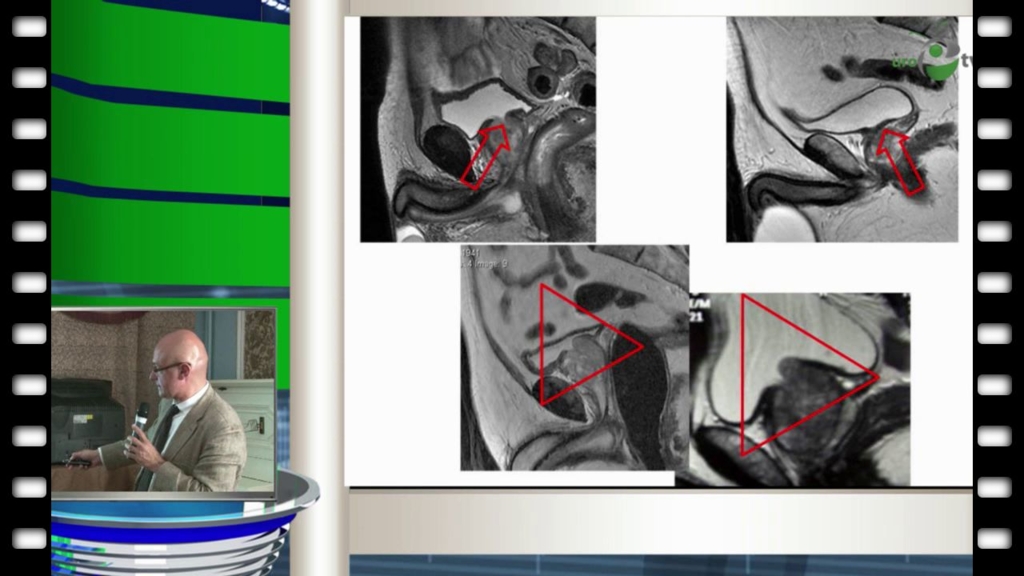

Пушкарь Д.Ю. - Робот-ассистированная радикальная простатэктомия: сложные случаи